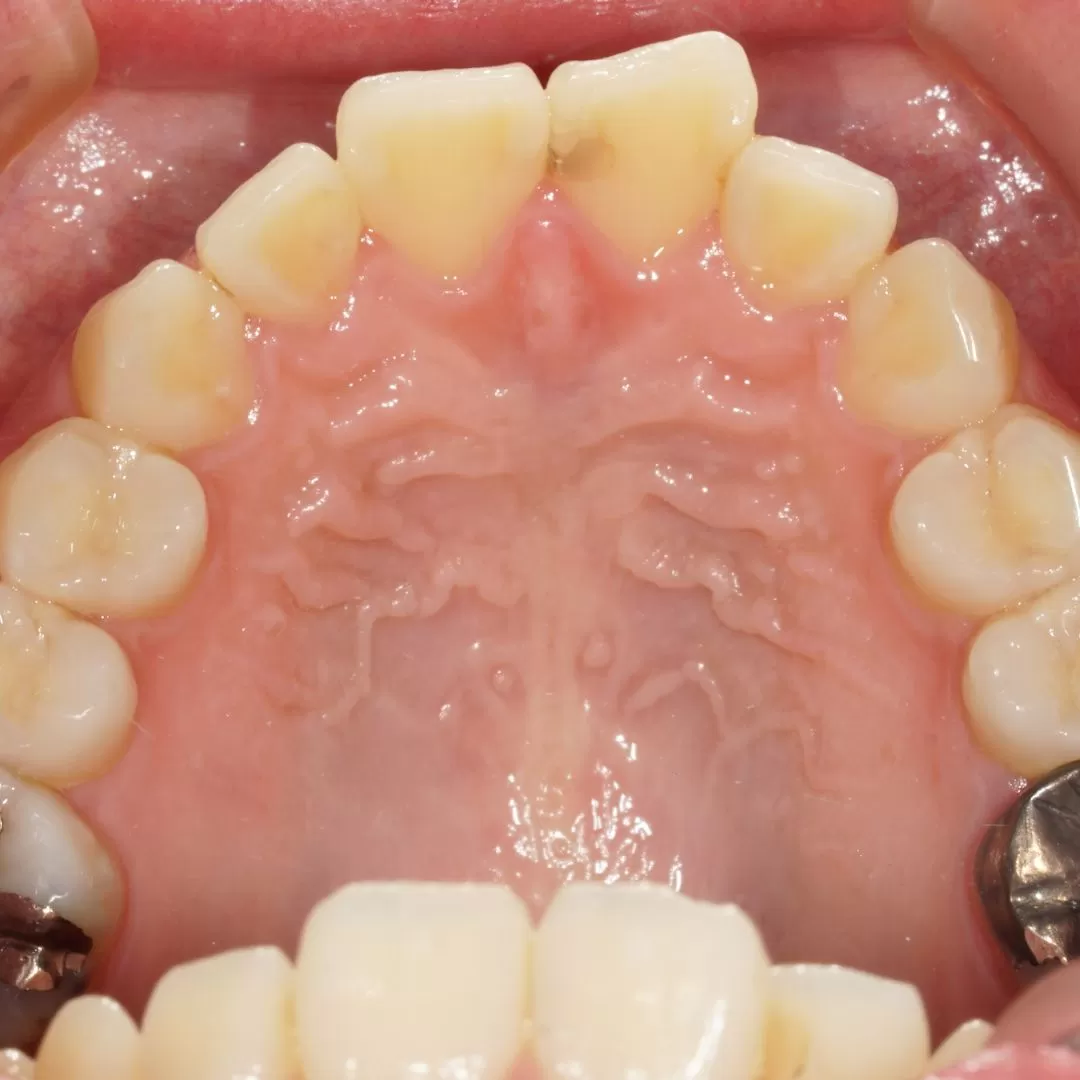

今回の症例ですがこのような状態を

このように歯茎に接する部分はぎりぎりに

このように装着してあります。

全周ラミネートべニア仕上げです。